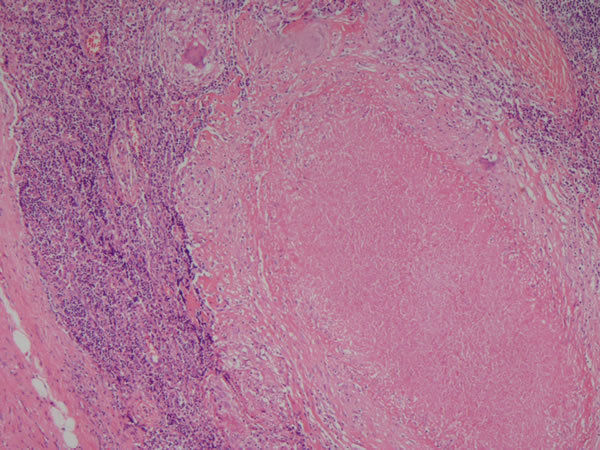

Linfonodo - tecido linfoide Necrose caseosa (parte rosinha no meio) - tuberculose ganglionar Causas: Histoplasmose, sarcoidose Outros achados: inflamação crônica (granuloma) |

Linfonodo -Tecido linfoide Necrose caseosa - tuberculose Outros achados: Infl. crônica - Granuloma epitelioide (rosinha, a parte roxa é normal) |

Linfonodo -Tecido linfoide Necrose caseosa (centro rosa)- tuberculose Outros achados: Infl. crônica - Granuloma epitelioide |